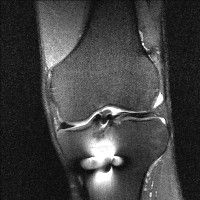

무릎 mri 간단히 봐주실 수 있으시나요 ㅠㅠ

안녕하세요 8년전 십자인대 수술하고 최근 무리한 운동에 무릎 불편감이 생겨서

mri 찍었습니다.

진단결과는 첫 찍은 병원에서 활액막염 이라는 진단을 받았습니다. 혹시 봐주실 수 있으실까요?

진단결과가 달라 혼란스럽습니다 ㅠㅠ

• 안녕하세요. 강성주 의사입니다.

올라온 MRI가 단편적이라서 정확한 진단에 어려움이 있지만 십자인대에는 큰 이상이 있지는 않은것 같으며, 무릎관절내 물이 있는 것으로 보아 활액막염의 진단이 맞을 것 같습니다.

하지만 단편적인 영상이기 때문에 촬영병원에서 정확한 판독지 등을 받으시는 것이 좋겠습니다.